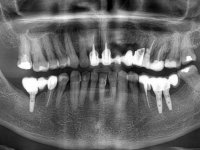

66-year-old male patient, non-smoker. It featured a 5-member metal-ceramic bridge with extreme mobility. Teeth 11 and 21 had infiltrated cervical margins. Both arches showed root exposure with signs of cervical abrasion. Composite resin “slots” were visible on the buccal surfaces of some mandibular teeth compatible with an orthodontic treatment with aligners that the patient was undergoing. After the imaging examination, it was found that the bridge's distal support, tooth 24, was irretrievably lost. The mesial pillars 11 and 21 had endodontic treatment and intraradicular posts. Teeth 25 and 26 also had endodontic treatment and extensive restorations in composite resin. In the lower jaw, two bridges were visible. In the third quadrant a 4-element bridge supported on tooth 35 and on 2 implants placed in the location of teeth 36 and 37. In the fourth quadrant a 3-element bridge supported on tooth 45 and an implant placed in the location of tooth 46. The patient presented a thick gingival phenotype and very good oral hygiene.

The patient was proposed to undergo a fixed oral rehabilitation consisting of a 2-element bridge over teeth 11 and 21 and a 5-element bridge over 3 implants that would be placed in the location of teeth 22, 24 and 26. The prosthetic structures would have an infrastructure in Zr coated with ceramic and the bridge over the implants would be screwed. The indicated extraction of teeth 25 and 26 and placement of an implant in the 26 site would imply surgery to fill the maxillary sinus. As the patient showed interest in having fixed temporary rehabilitation during treatment, we divided the treatment into 6 phases to achieve this goal: 1- Placement of a temporary bridge over teeth 11,21,25 and 26. With tooth extraction 24. 2- Placement of 2 implants in the location of teeth 22 and 24. 3- Placement of a temporary 6-element bridge over teeth 11 and 21 and over the implants. 4- Carrying out surgery to fill the maxillary sinus. 5 – Placement of the implant in the location of tooth 26 and in the area where the filling of the maxillary sinus was made. 6 – Placement of the definitive work.

A temporary acrylic bridge made in the laboratory with 7 elements was made, with teeth 11,21, 25 and 26 as pillars. The old bridge was removed and tooth 24 was extracted. The provisional bridge after relining was cemented in the mouth. Two implants were placed in the teeth 22 and 24 and 3 months after this intervention an impression was made to make a temporary bridge screwed over the implants and cemented to the teeth. The bridge was placed in the mouth and teeth 25 and 26 were extracted. 3 months later, surgery was performed to fill the maxillary sinus and 6 months later the implant was placed in the location of tooth 26. After osseointegration of this implant, the final impression was made for the final work. The bridge over the implants was permanently screwed on and the bridge over the teeth was cemented with resin-reinforced glass ionomer cement.